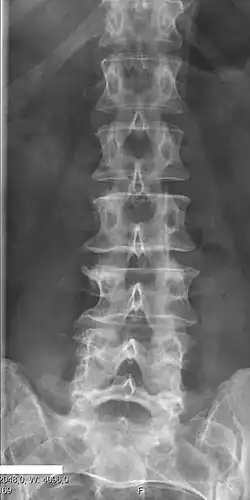

Several congenital block vertebrae in the transition from the thoracic to the lumbar spine and hemivertebrae. -

Congenital block vertebra in the lumbar spine (partial vertebrae 3 and 4). The rear portion of the disc still exists. -